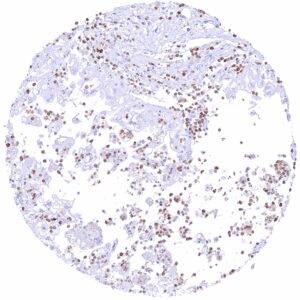

| Bone marrow/ lymphoid tissue | Bone marrow | Strong membranous CD35 staining of a subset of cells. |

In normal tissues, CD35 is most highly expressed in normal follicular dendritic cells, but it can also be seen on lymphocytes of various types, macrophages, granulocytes, and erythrocytes.

| Remarks | Scattered CD35 positive inflammatory cells can be seen in all tissues. |